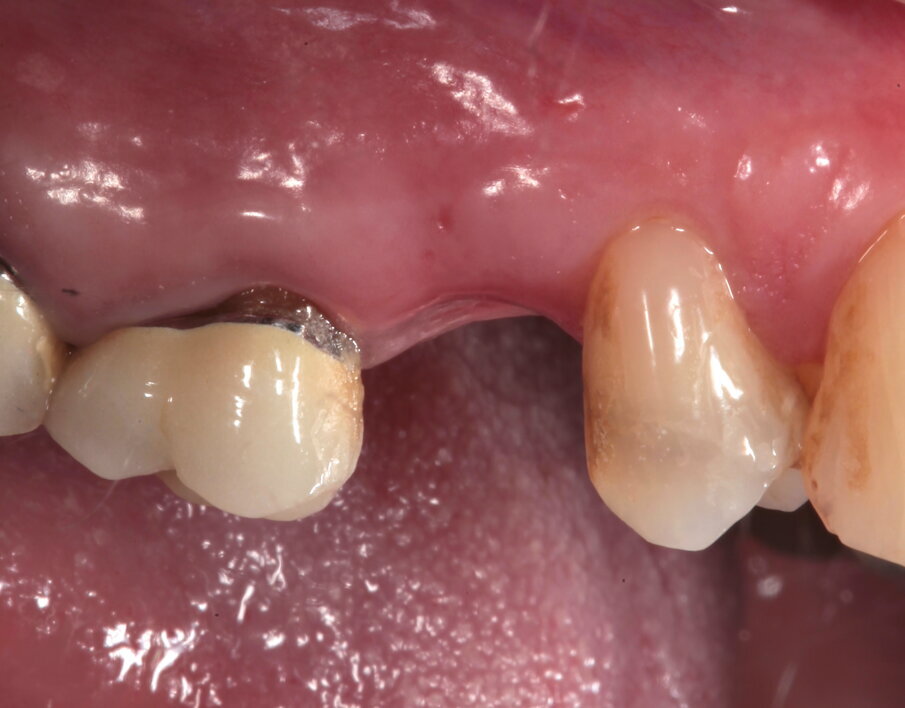

La paziente si presenta in visita lamentando mobilità e l’insorgenza di un dolore alla masticazione a carico dell’elemento 25. Clinicamente l’elemento presenta una corona in ceramica integrale realizzata anni prima (non ricorda quanti) presso altra sede, mobilità di II grado e sondaggio di 9 mm sul versante palatale.

Si presenta inoltre dolente alla percussione. Si riscontra anche l’assenza di risposta al test di vitalità dell’elemento 24, sul quale la paziente riferisce sia stata effettuata una medicazione endodontica da un collega come tentativo di risolvere la sintomatologia dolorosa a carico dell’elemento 25 (Figg. 1-3).

Si effettua prima una lastra endorale e in seguito una CBCT dell’elemento per valutare le possibilità di ritrattamento endodontico e la morfologia del difetto osseo, dalle quali si evince come le corticali appaiono essere mantenute ma che la porzione midollare dell’osso alveolare risulti completamente riassorbita. Gli elementi 26 e 27 presentano terapie endodontiche incongrue ma essendo asintomatici e privi di lesioni periapicali si sceglie insieme alla paziente di tenerli monitorati (Figg. 4, 5).